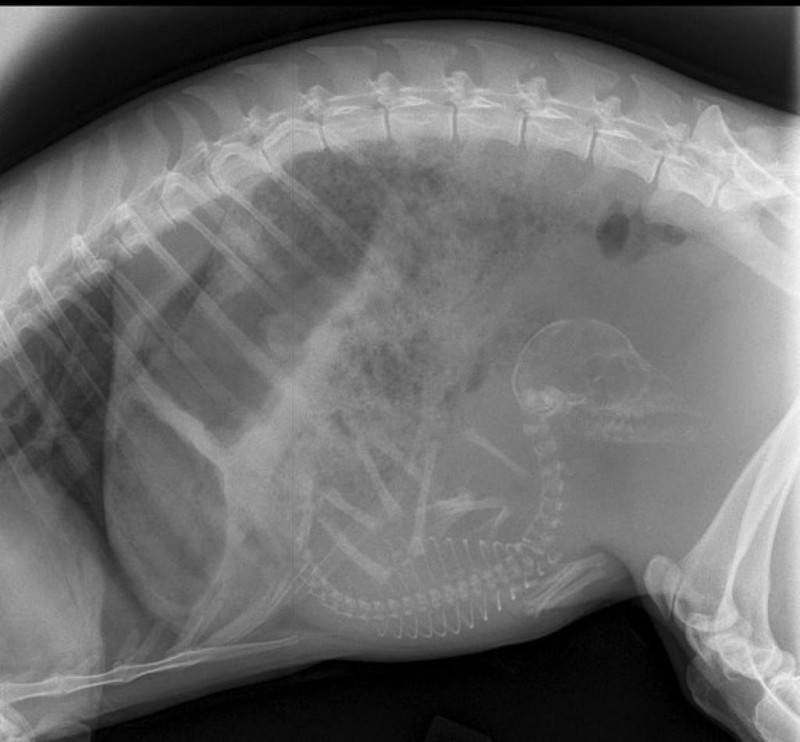

Хээл авсан амьтадын хэвлийн рентген зураг ингэж харагддаг. Хэдий итгэмээргүй ч ийм л байна.